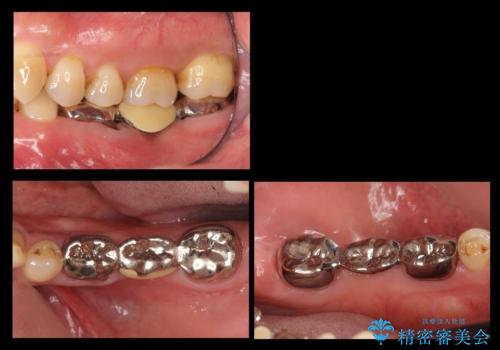

割れてしまった奥歯をインプラントで 気になる銀歯もセラミッククラウンで審美的に

臼歯部インプラント・再補綴